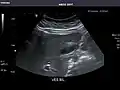

Renal ultrasonography

Ultrasonography of the kidneys is essential in the diagnosis and management of kidney-related diseases. The kidneys are easily examined, and most pathological changes in the kidneys are distinguishable with ultrasound.[7]

Kidneys: Right and left kidneys measure 11.5 cm and 12 cm in length respectively. No hydronephrosis. Small left lower pole kidney cyst.